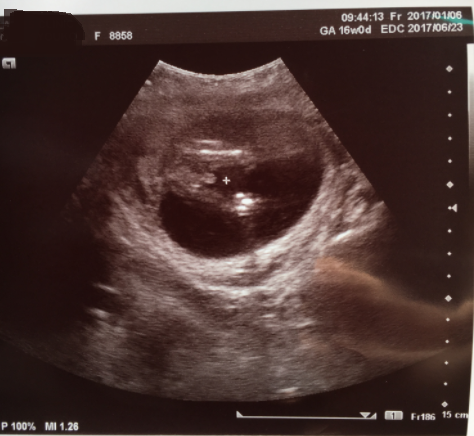

16週0日(16w0d・男の子)|ここ☆つばさ さん(28歳)

エコー写真撮影時のエピソード:

今まではお腹にエコーを当ててみるのではなかって初めてのお腹にエコーを当てて撮った写真。 凄く緊張していたけど動いてるのを観るのが楽しみでした。

毎回エコーで両手で頭をかいていたり顔を隠す仕草やエコーに向かって笑っているであろう写真が撮れて先生に『毎回いろんなポーズをしてくれるね』と言われたりしました。 旦那にも報告し2人で笑ったりしていました。